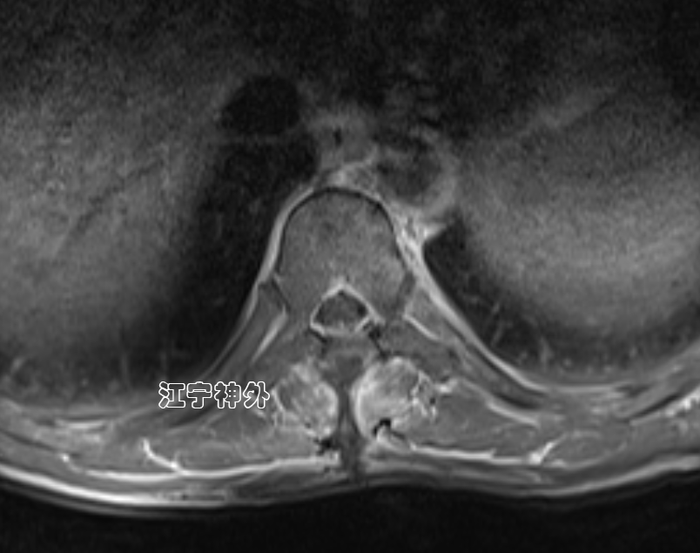

郑主任阅片发现,从横断面来看,肿瘤几乎占据了椎管全径,正常的脊髓圆锥和神经根已不可辨认,很难说是髓外硬膜下病变还是髓内病变。结合病程很长,脑脊液循环已完全阻断,推测肿瘤与脊髓圆锥、马尾神经根之间,以及肿瘤与硬脊膜之间很可能有明显粘连,所以手术难度较大,手术风险高。

经过充分的术前准备,郑学胜团队于2月16日在术中电生理监测下实施椎管肿瘤切除术;结果手术难度比预估的还要更大,因为不仅肿瘤质地很硬、血供丰富,而且肿瘤位于脊髓圆锥和神经根的腹侧,手术只能在圆锥和神经根的间隙里操作,肿瘤的腹侧又与硬脊膜严重粘连;郑学胜团队经过近6小时的手术,终于将肿瘤完整全切,并且脊髓圆锥和神经根保护良好。

术后磁共振显示,肿瘤无任何残留,脊髓圆锥和神经根恢复正常形态,术后大小便功能、下肢运动恢复正常。术后病理提示:神经鞘瘤伴出血。